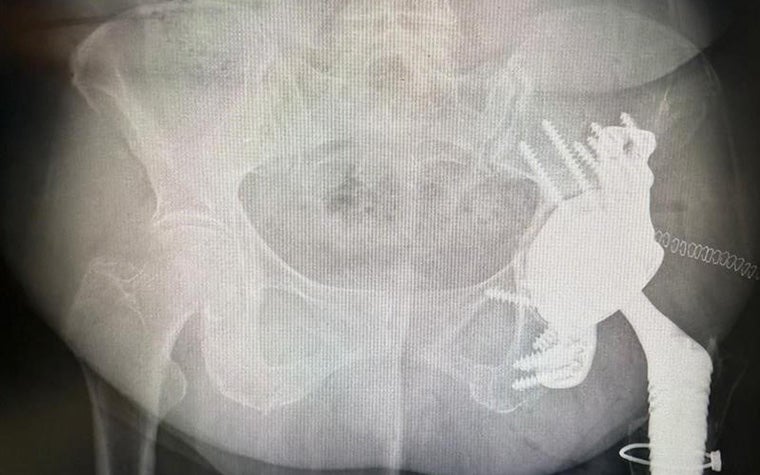

The aMace implant helps surgeons break the revision cycle. It is designed for minimal risk of dislocation, is based on unique 3D pelvis analyses to quantify bone loss and available bone stock, and makes long-term fixation possible with crossed screw trajectories and a defect-filling porous augment.

Naturally, complex cases present obstacles, but Dr. Van Overschelde emphasizes the importance of thorough preparation and close collaboration with the clinical engineers: “Smooth communication and accurate planning from Materialise’s engineers give me confidence in the precision of the implant fit and screw planning. The SurgiCase online platform also gives us a very detailed overview, which helps us resolve any potential issues before entering the OR.”

For this particular case, the team included an important modification to the implant design based on these insights: a polished surface on the anterior side to avoid irritating the surrounding soft tissue.

This comprehensive preparation was a major contributor to Dr. Van Overschelde executing the surgery successfully. He immediately felt very confident in the result: “I expected the reconstruction to be very stable, allowing the patient to fully bear weight and regain mobility immediately."

“At 7 am the day after the surgery, the patient was already standing and washing up at the sink. It’s a remarkable testament to the immediate impact of the implant and the procedure.”